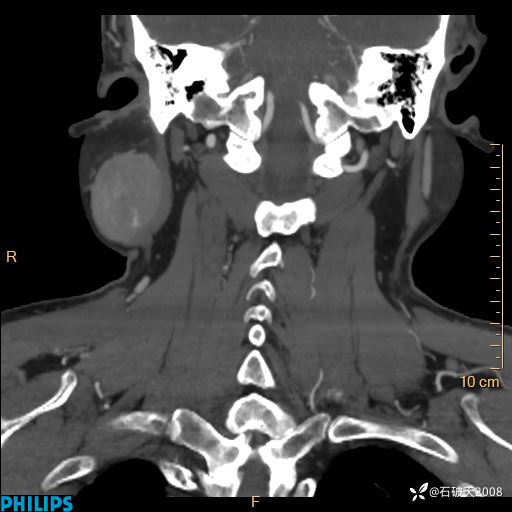

MIP